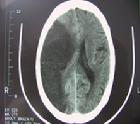

1.腦CT掃描腦梗死的腦CT掃描的主要表現為:①病灶的低密度:是腦梗死重要的特徵性表現此徵象可能系腦組織缺血性水腫所致②局部腦組織腫脹:表現為腦溝消失腦池、腦室受壓變形,中線結構向對側移位即腦CT掃描顯示有占位效應此徵象可在發病後4~6h觀察到③緻密動脈影:為主要腦

腦梗死2.腦MRI檢查能較早期發現腦梗死,特別是腦幹和小腦的病灶。T1和T2馳像時間延長加權圖像上T1在病灶區呈低信號T2呈高信號腦MRI檢查能發現較小的梗死病灶腦MRI彌散成像能反映新的梗死病變。MRI在缺血性腦梗死早期診斷和鑑別診斷的評價中已顯示出優勢,近年來超導高檔磁共振設備投入臨床套用,基於平面回波(EPI)技術的磁共振彌散加權成像(DWI)及血流灌注加權成像(PWI)的套用,對腦梗死的早期診斷,甚至在急性腦梗死區血流灌注變化以及病理生理過程的相關性研究都取得了一定進展